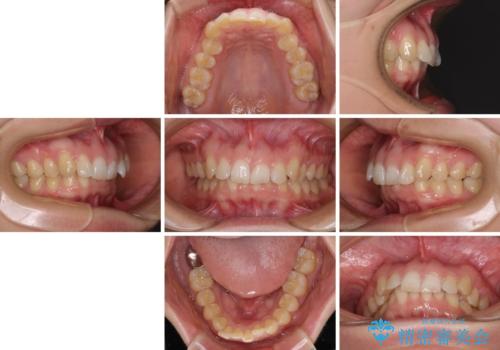

カリエール・ディスタライザーとインビザラインを用いた前歯の咬み合わせ改善

- 上顎前歯の前方に傾斜した咬み合わせを気にして来院された患者様です。

奥歯の咬み合わせを見ると、上顎が下顎に対して相対的に前方にありました。

深い咬み合わせを改善するためには、上顎臼歯を後方に移動させつつ、下顎の小臼歯を直立させる必要があります。

インビザライン単体で対応ることも検討できますが、達成する可能性が低いため、カリエールディスタライザーという補助装置を併用して、より確実性を上げることとしました。

奥歯の咬み合わせと深い咬み合わせを改善した後、インビザラインで歯列を整えることとしました。

カリエールディスタライザーや部分的なワイヤー矯正を併用したことで、確実かつ短期間で治療を終えることができました。